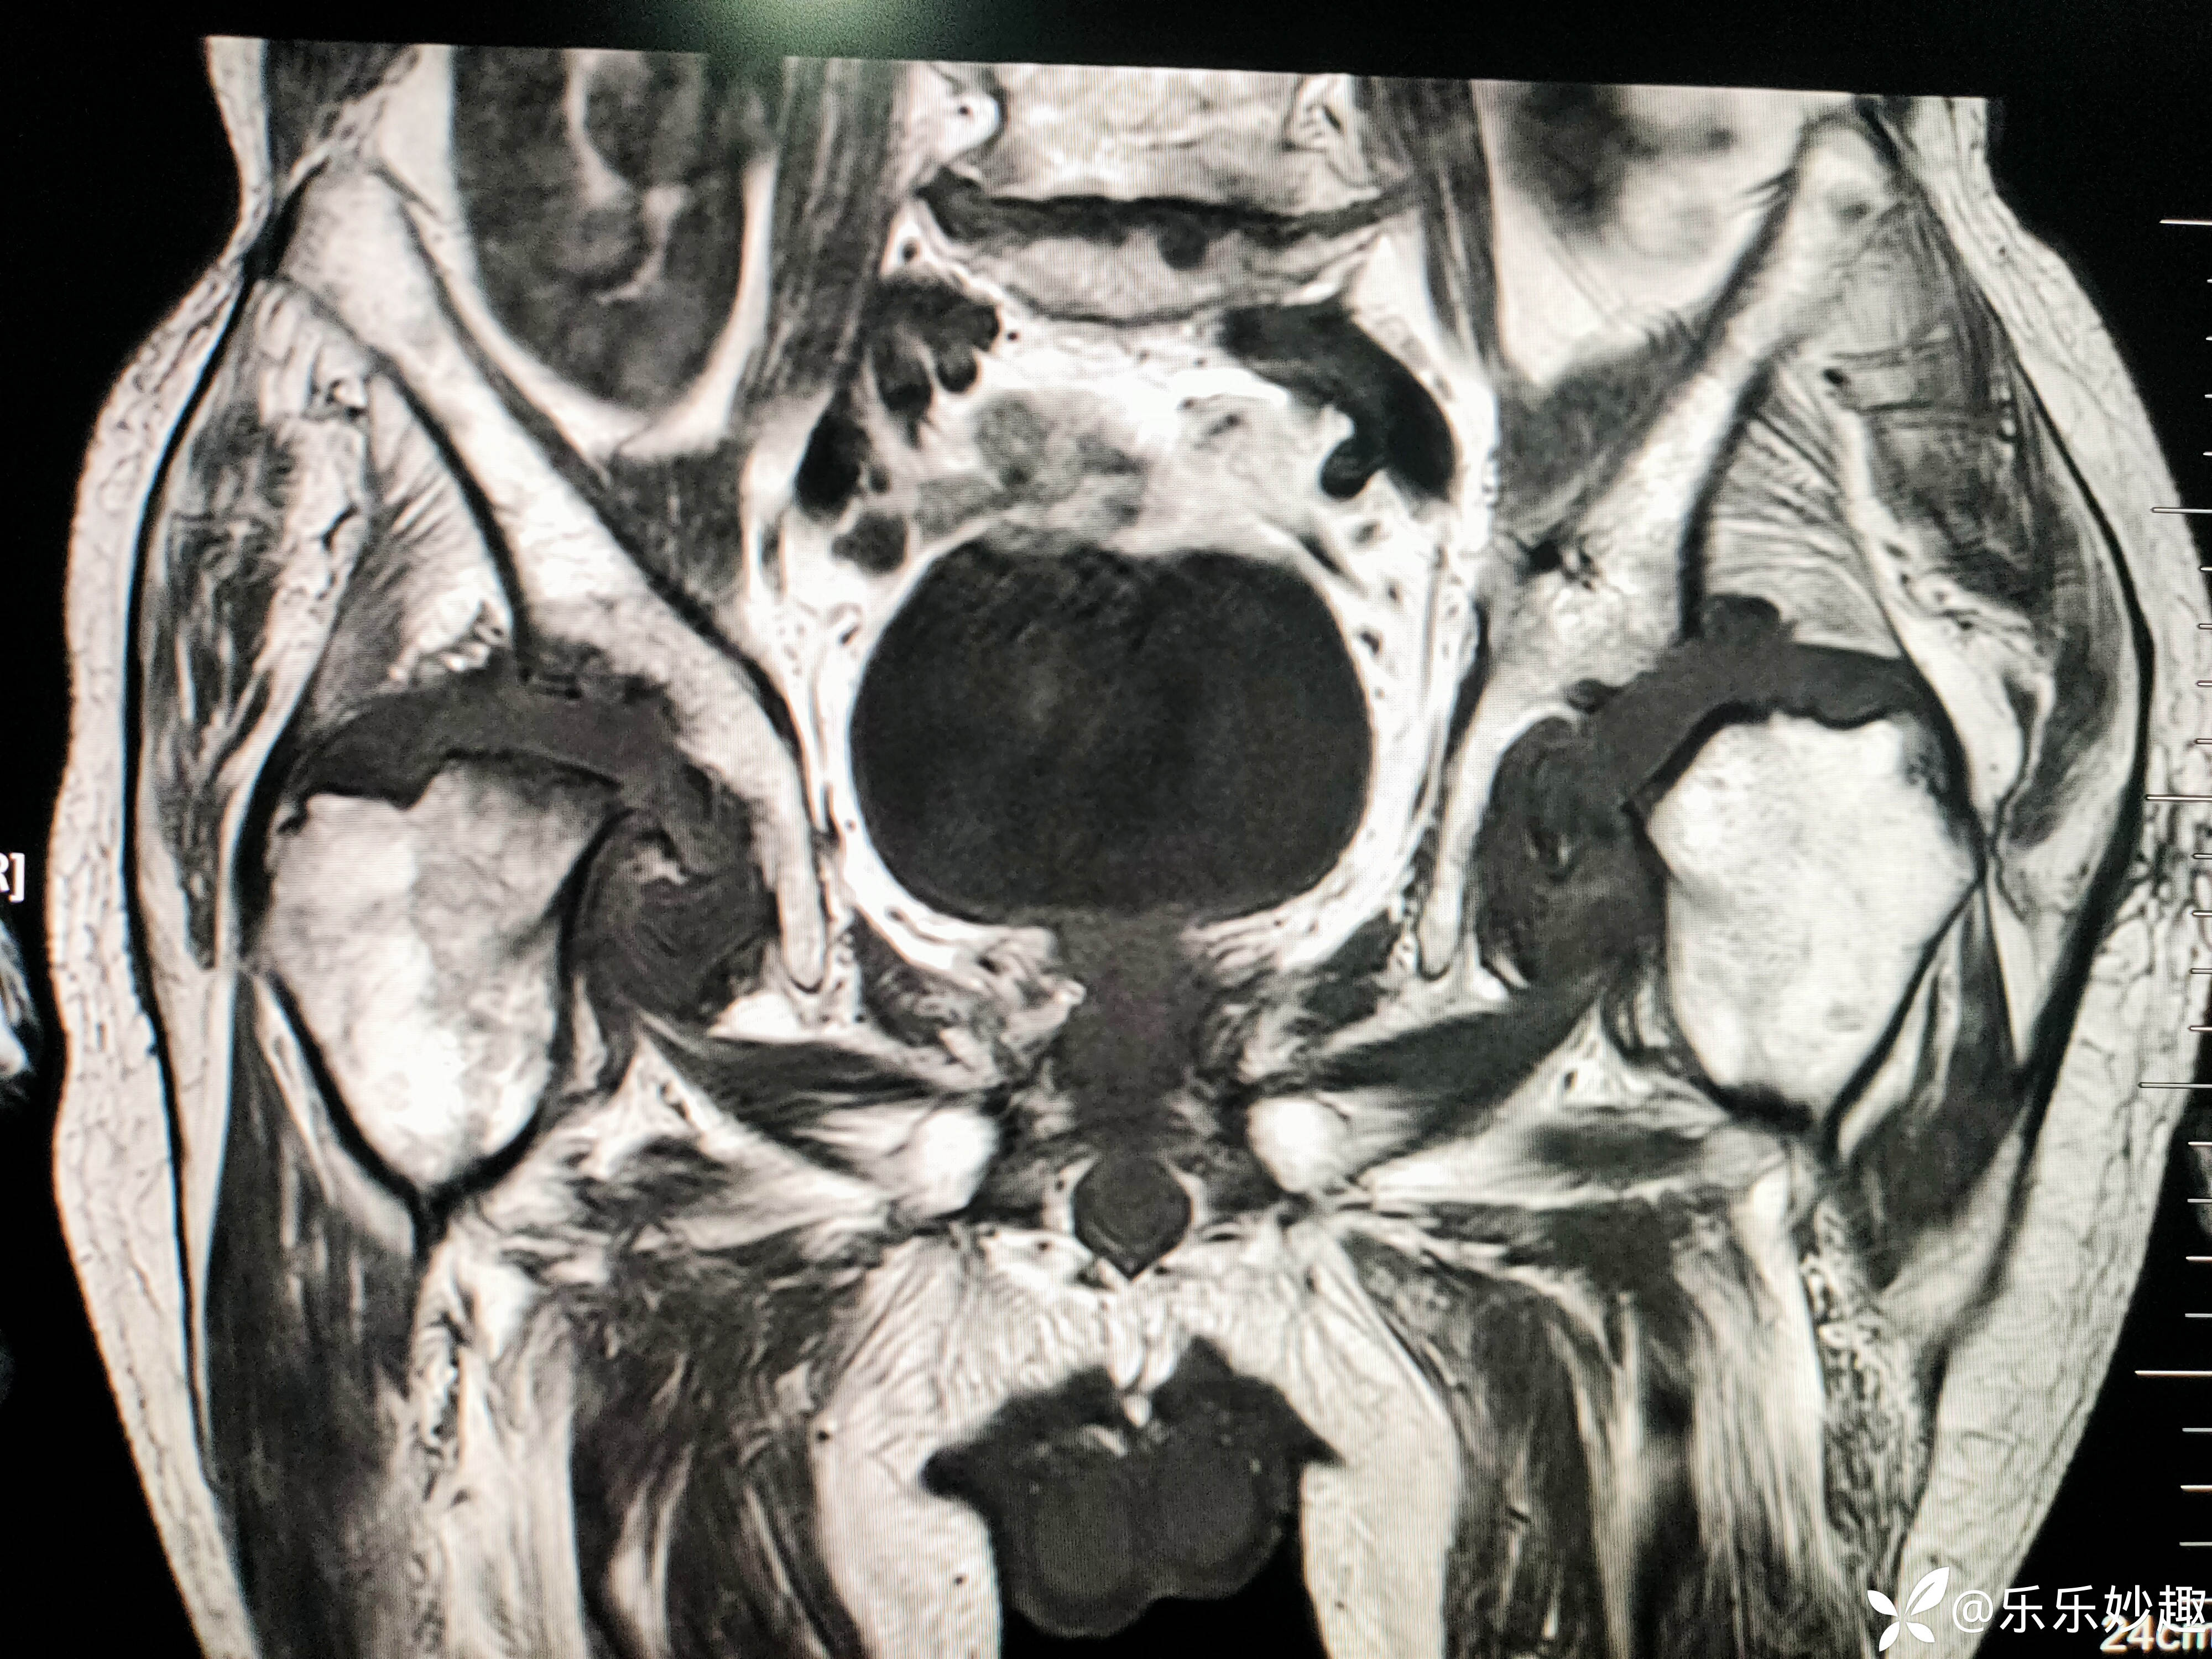

最后做了髋关节MR,见下图